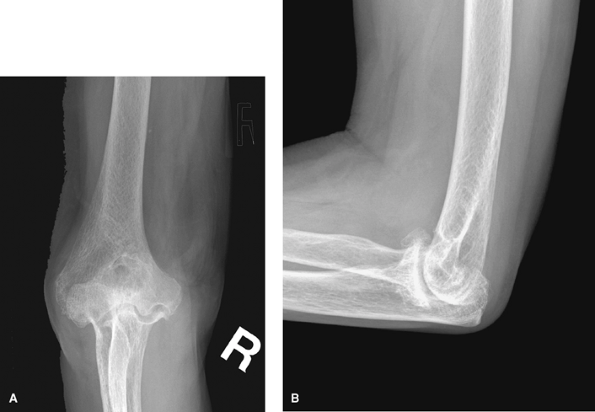

![]() |

Figure 62-3 A: Stage II rheumatoid arthritis. B: Stage II rheumatoid arthritis.